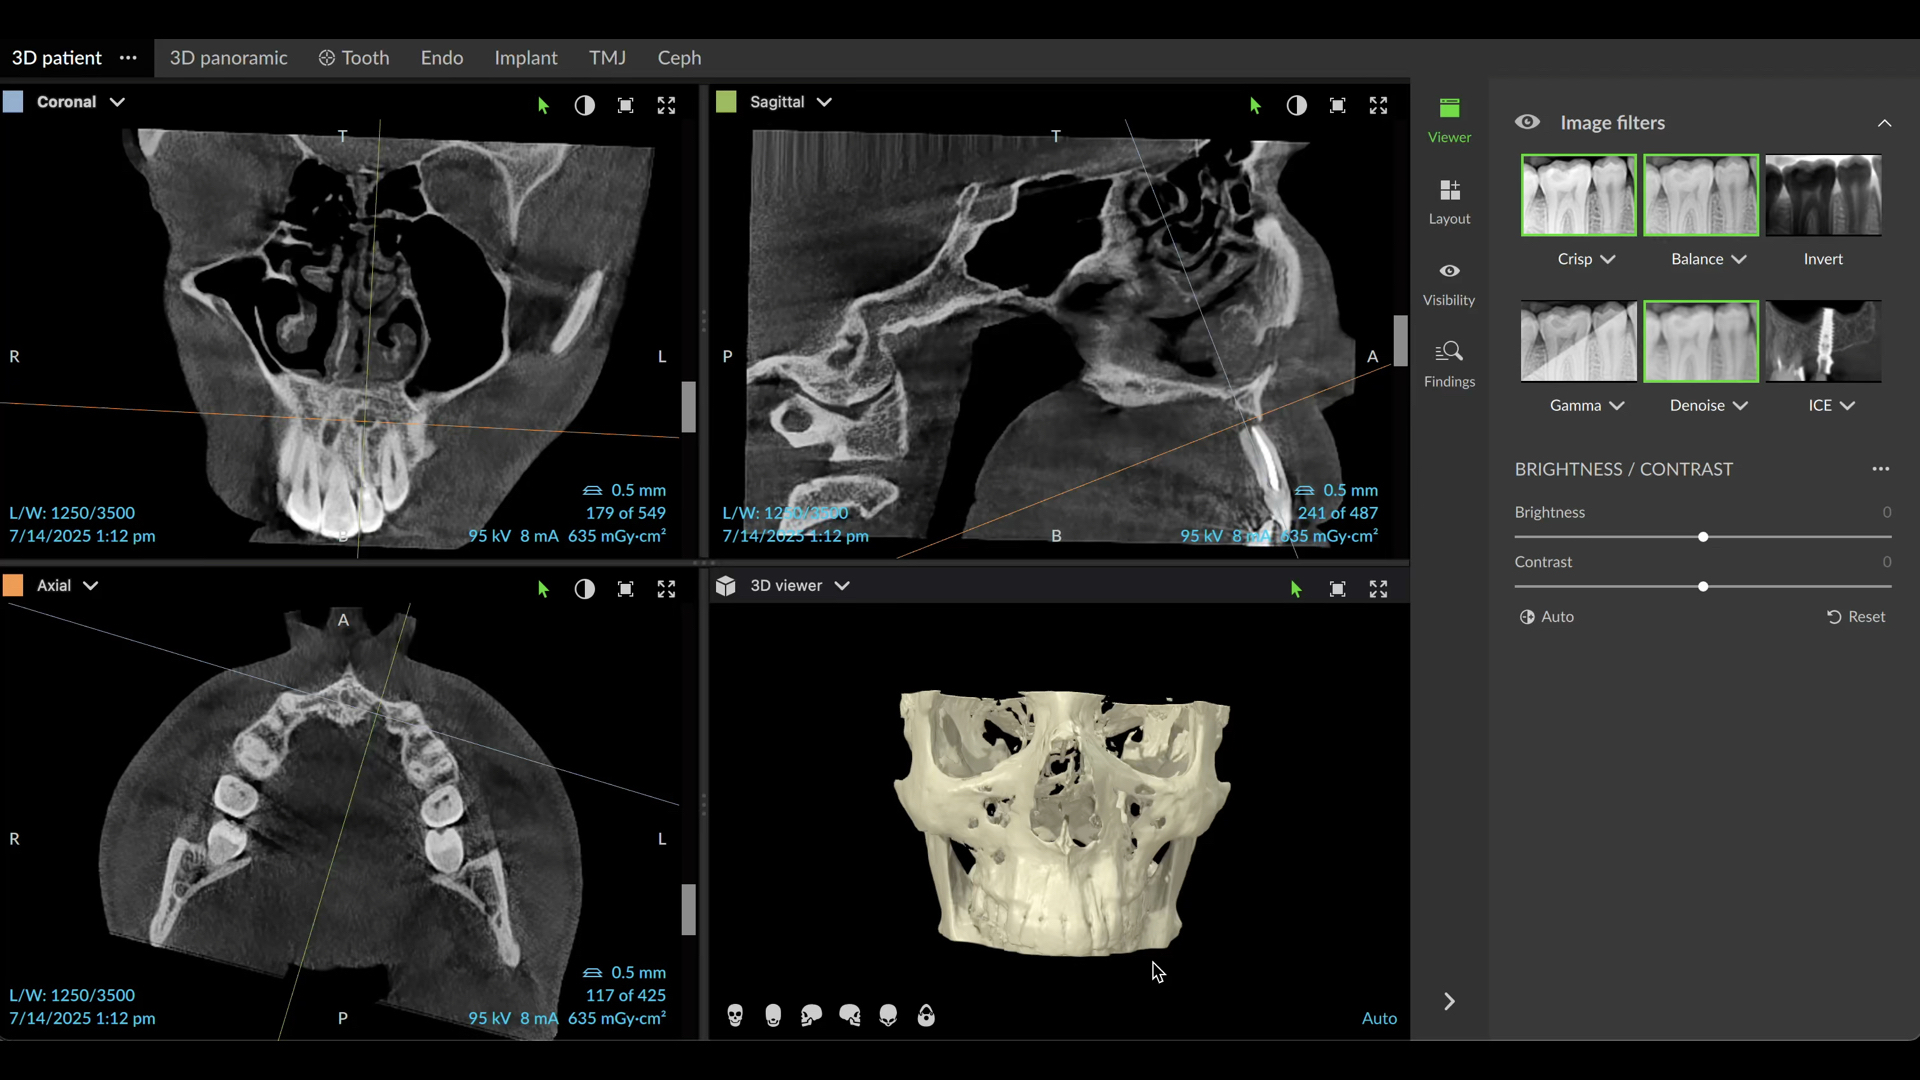

The patient presented for assessment of a fistula in the anterior maxilla on a radiograph, appearing as a large lesion above the lateral incisor (Fig. 1). The patient recalled having been hit by a ball a long time before. A CBCT scan was taken, and it showed a large cystic lesion destroying a large portion of the anterior maxilla. Owing to the edge-enhancing capability of the DTX software provided by artificial intelligence, we can enhance the quality of the image. Since the CBCT scan was taken in a different centre, we imported the DICOM file into the DTX software. The image clearly showed the nerve entering the central incisor and a thin layer of bone covering the apex, and the nerve and periodontal ligament in this area were intact (Fig. 2).

Fig. 2a: CBCT images showing the size of the lesion and destruction of both cortical walls. Artificial intelligence-enhanced image.

Fig. 2b: Artificial intelligence-enhanced image showing the nerve entering the central incisor.

Fig. 2c: Original image.

Fig. 2d: Original image.